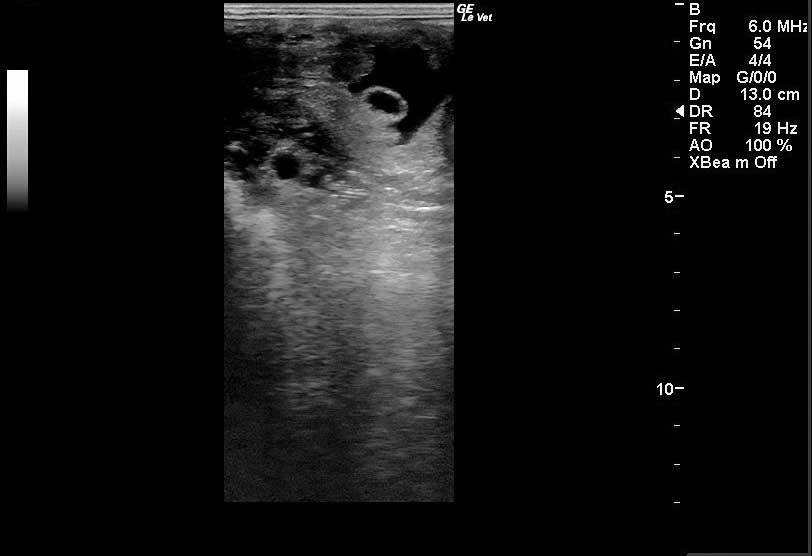

Once palpation is completed, one can progress to transrectal ultrasound examination of the reproductive tract (Ginther and Pierson, 1983). This is most commonly undertaken using a 5MHz or 7.5MHz linear array transducer. The veterinarian should assess the echotexture and diameter of the uterine body and horns, looking particularly for evidence of endometrial cysts (Stanton et al, 2004; Figure 1) and of intrauterine fluid accumulations.

The position and size of any cysts should be recorded, as should the depth, location and echogenicity of any fluid. As examples, cysts that are small and discrete are likely to have less impact on a mare’s ability to remain pregnant than a large group of cysts situated where the embryo nidates at the base of the uterine horn, which may inhibit movement of the early embryo throughout the uterus, and subsequently disrupt placental transfer.

Purulent fluid within the uterus generally has a fairly hyperechoic appearance; fluid that is the result of “urine pooling” in the vagina and subsequent aspiration through the cervix into the uterus is commonly found extending from the cervix into the uterine body.